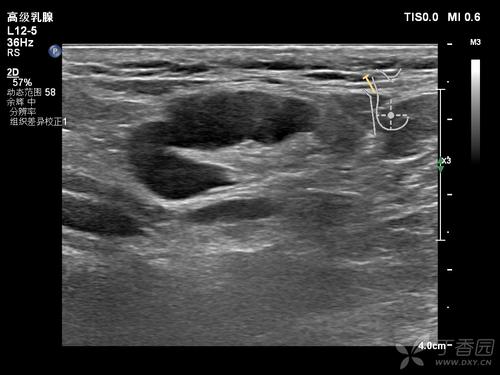

在B超下长这样的:

这种很可能就是肿瘤,而且十有八九是恶性的哟。